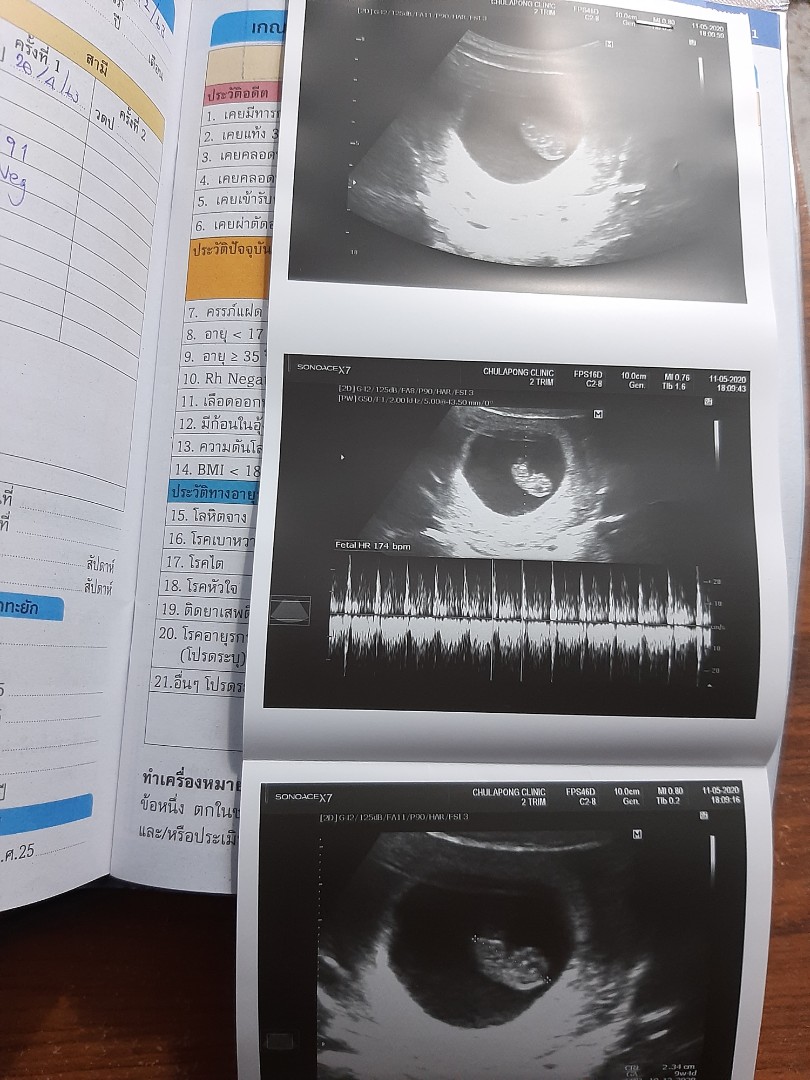

8w. เดือนธันวา จ้า